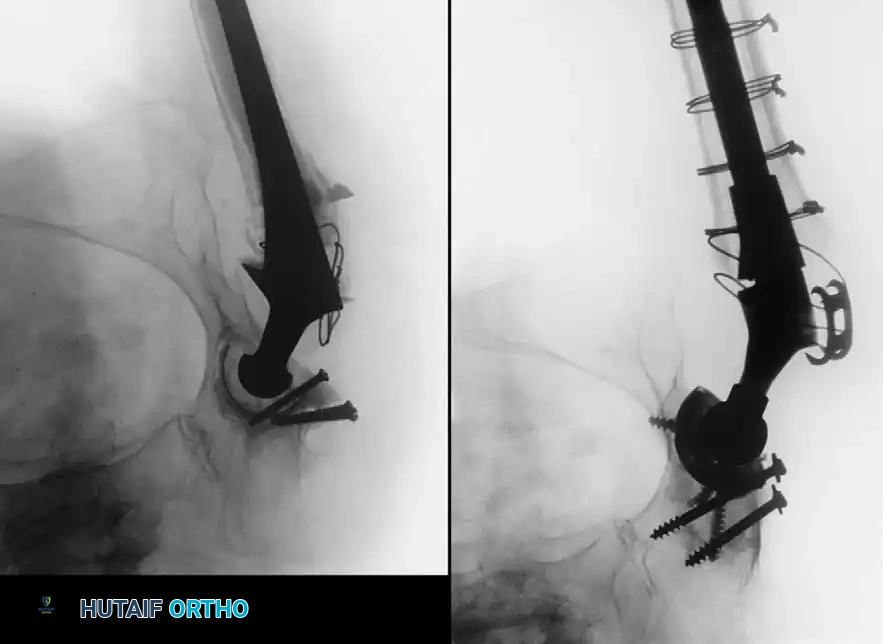

Acetabular Reconstruction

The goal of acetabular revision is to restore the anatomic center of rotation, achieve rigid initial fixation, and provide a biologic environment for long-term stability. Defects are classified using the Paprosky system.

- Type I & II Defects (Cavitary): Managed with hemispherical, highly porous-coated "jumbo" cups (typically >62 mm) and particulate cancellous autograft/allograft. Multiple screws are utilized in the safe zone (posterosuperior quadrant) to achieve rigid primary fixation.

- Type III Defects (Segmental/Severe): Require advanced techniques. Trabecular metal augments are used to fill superior segmental defects and support the cup. In cases of pelvic discontinuity, a cup-cage construct or custom triflange acetabular component may be necessary.

Femoral Reconstruction

Femoral bone loss dictates stem selection. The fundamental biomechanical principle of femoral revision is to achieve rigid fixation in healthy, diaphyseal bone, bypassing the proximal deficiency by a minimum of two cortical diameters (typically 4-6 cm).

2. Modular Fluted Tapered Stems: The modern workhorse for severe (Type III and IV) defects. The flutes provide rotational stability, while the 2-to-3 degree taper achieves axial stability via three-point fixation in the diaphysis. Modularity allows independent adjustment of version, offset, and leg length after the distal stem is rigidly seated.

Pitfall: When seating a diaphyseal-engaging stem, prophylactic cerclage cabling of the distal femur is highly recommended to prevent catastrophic intraoperative splitting of the diaphysis during final impaction.